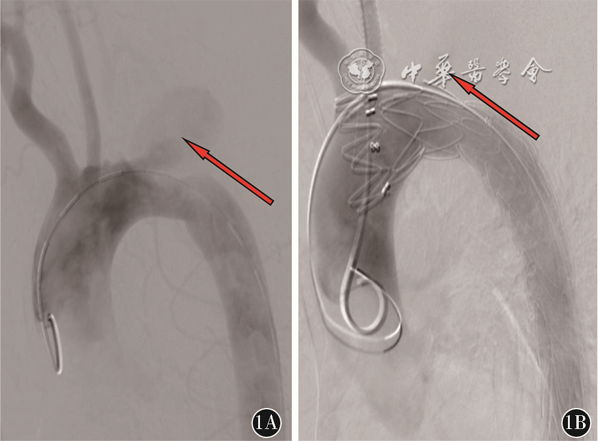

从患者突发呕血伴失血性休克可以判断该患者存在AEF。AEF 是指主动脉与邻近消化道发生的病理性相通,是一种少见的危及生命的疾病,该疾病最早由Cooper在1822年提出[4]。AEF 分为原发性和继发性两类。继发性AEF是指腹主动脉移植物重建术后发生的移植物侵蚀消化道形成的穿透性病变,相对于原发性AEF,继发性AEF发生率较高,但是发病率还是很低的,文献提示EVAR术后继发性AEF发病率为0.6%~2.0%[5]。继发性AEF的病因较多,目前考虑如下几个方面:(1)感染:术中操作感染、血性感染、邻近感染组织直接蔓延;(2)移植物:移植物材料、移植物形态、移植物断裂或成角、免疫排除反应;(3)机械:随着血管搏动移植物对血管消化道反复机械损伤;(4)患者:自身免疫病、营养不良、高龄等;(5)内漏:存在内漏,瘤囊增大损伤邻近消化道[6]。该患者自3年前术后一直未进行过复查,故无法明确是移植物的机械损伤还是存在内漏可能,查阅其3年前术中DSA影像(图1)、手术记录提示存在膜型内漏(即Ⅳ型内漏)。结合本次CTA见支架形态良好,原瘤囊未见扩张。故初步判断该患者发生继发性AEF原因为机械损伤可能性大。如处理不及时,将导致消化道大出血、移植物感染,最终导致死亡。继发性AEF的临床表现有发热、黑便及呕血。该患者近半年有间断发热,自行口服退烧药后缓解。大部分患者可有特征性的“前哨性出血”,这是一种间断性的轻中度出血,是大出血的前兆。“前哨性出血”的出血时间长短不一,短可至几小时,长可至几个月[7]。该患者自述的“咯血”不除外是“前哨性出血”,如果是“前哨性出血”,那么该患者从“前哨性出血”到大出血时间为6个月,时间较长,属临床罕见病例,这也给早期临床诊断带来了困难。